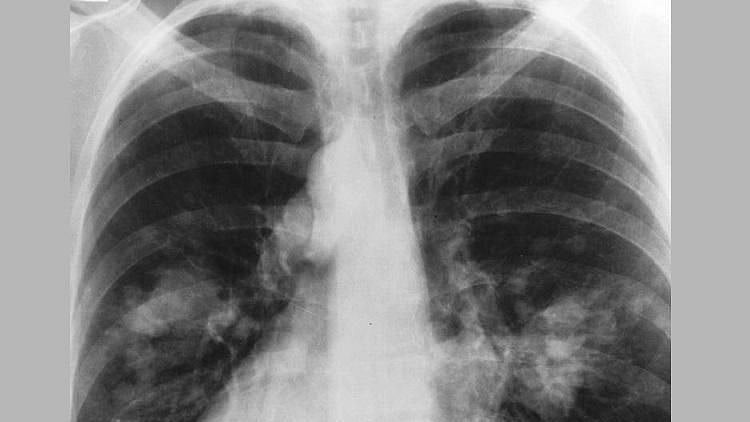

Pneumonia is a condition affecting the lungs in which the airspaces are inflamed. An individual with pneumonia might have fever and chills, cough, shortness of breath or other breathing difficulties.

Influenza is known to be one of the most common causes of pneumonia. Individuals found to be positive for coronavirus disease many times develop pneumonia, which has been known to be fatal in elderly individuals with COVID-19.